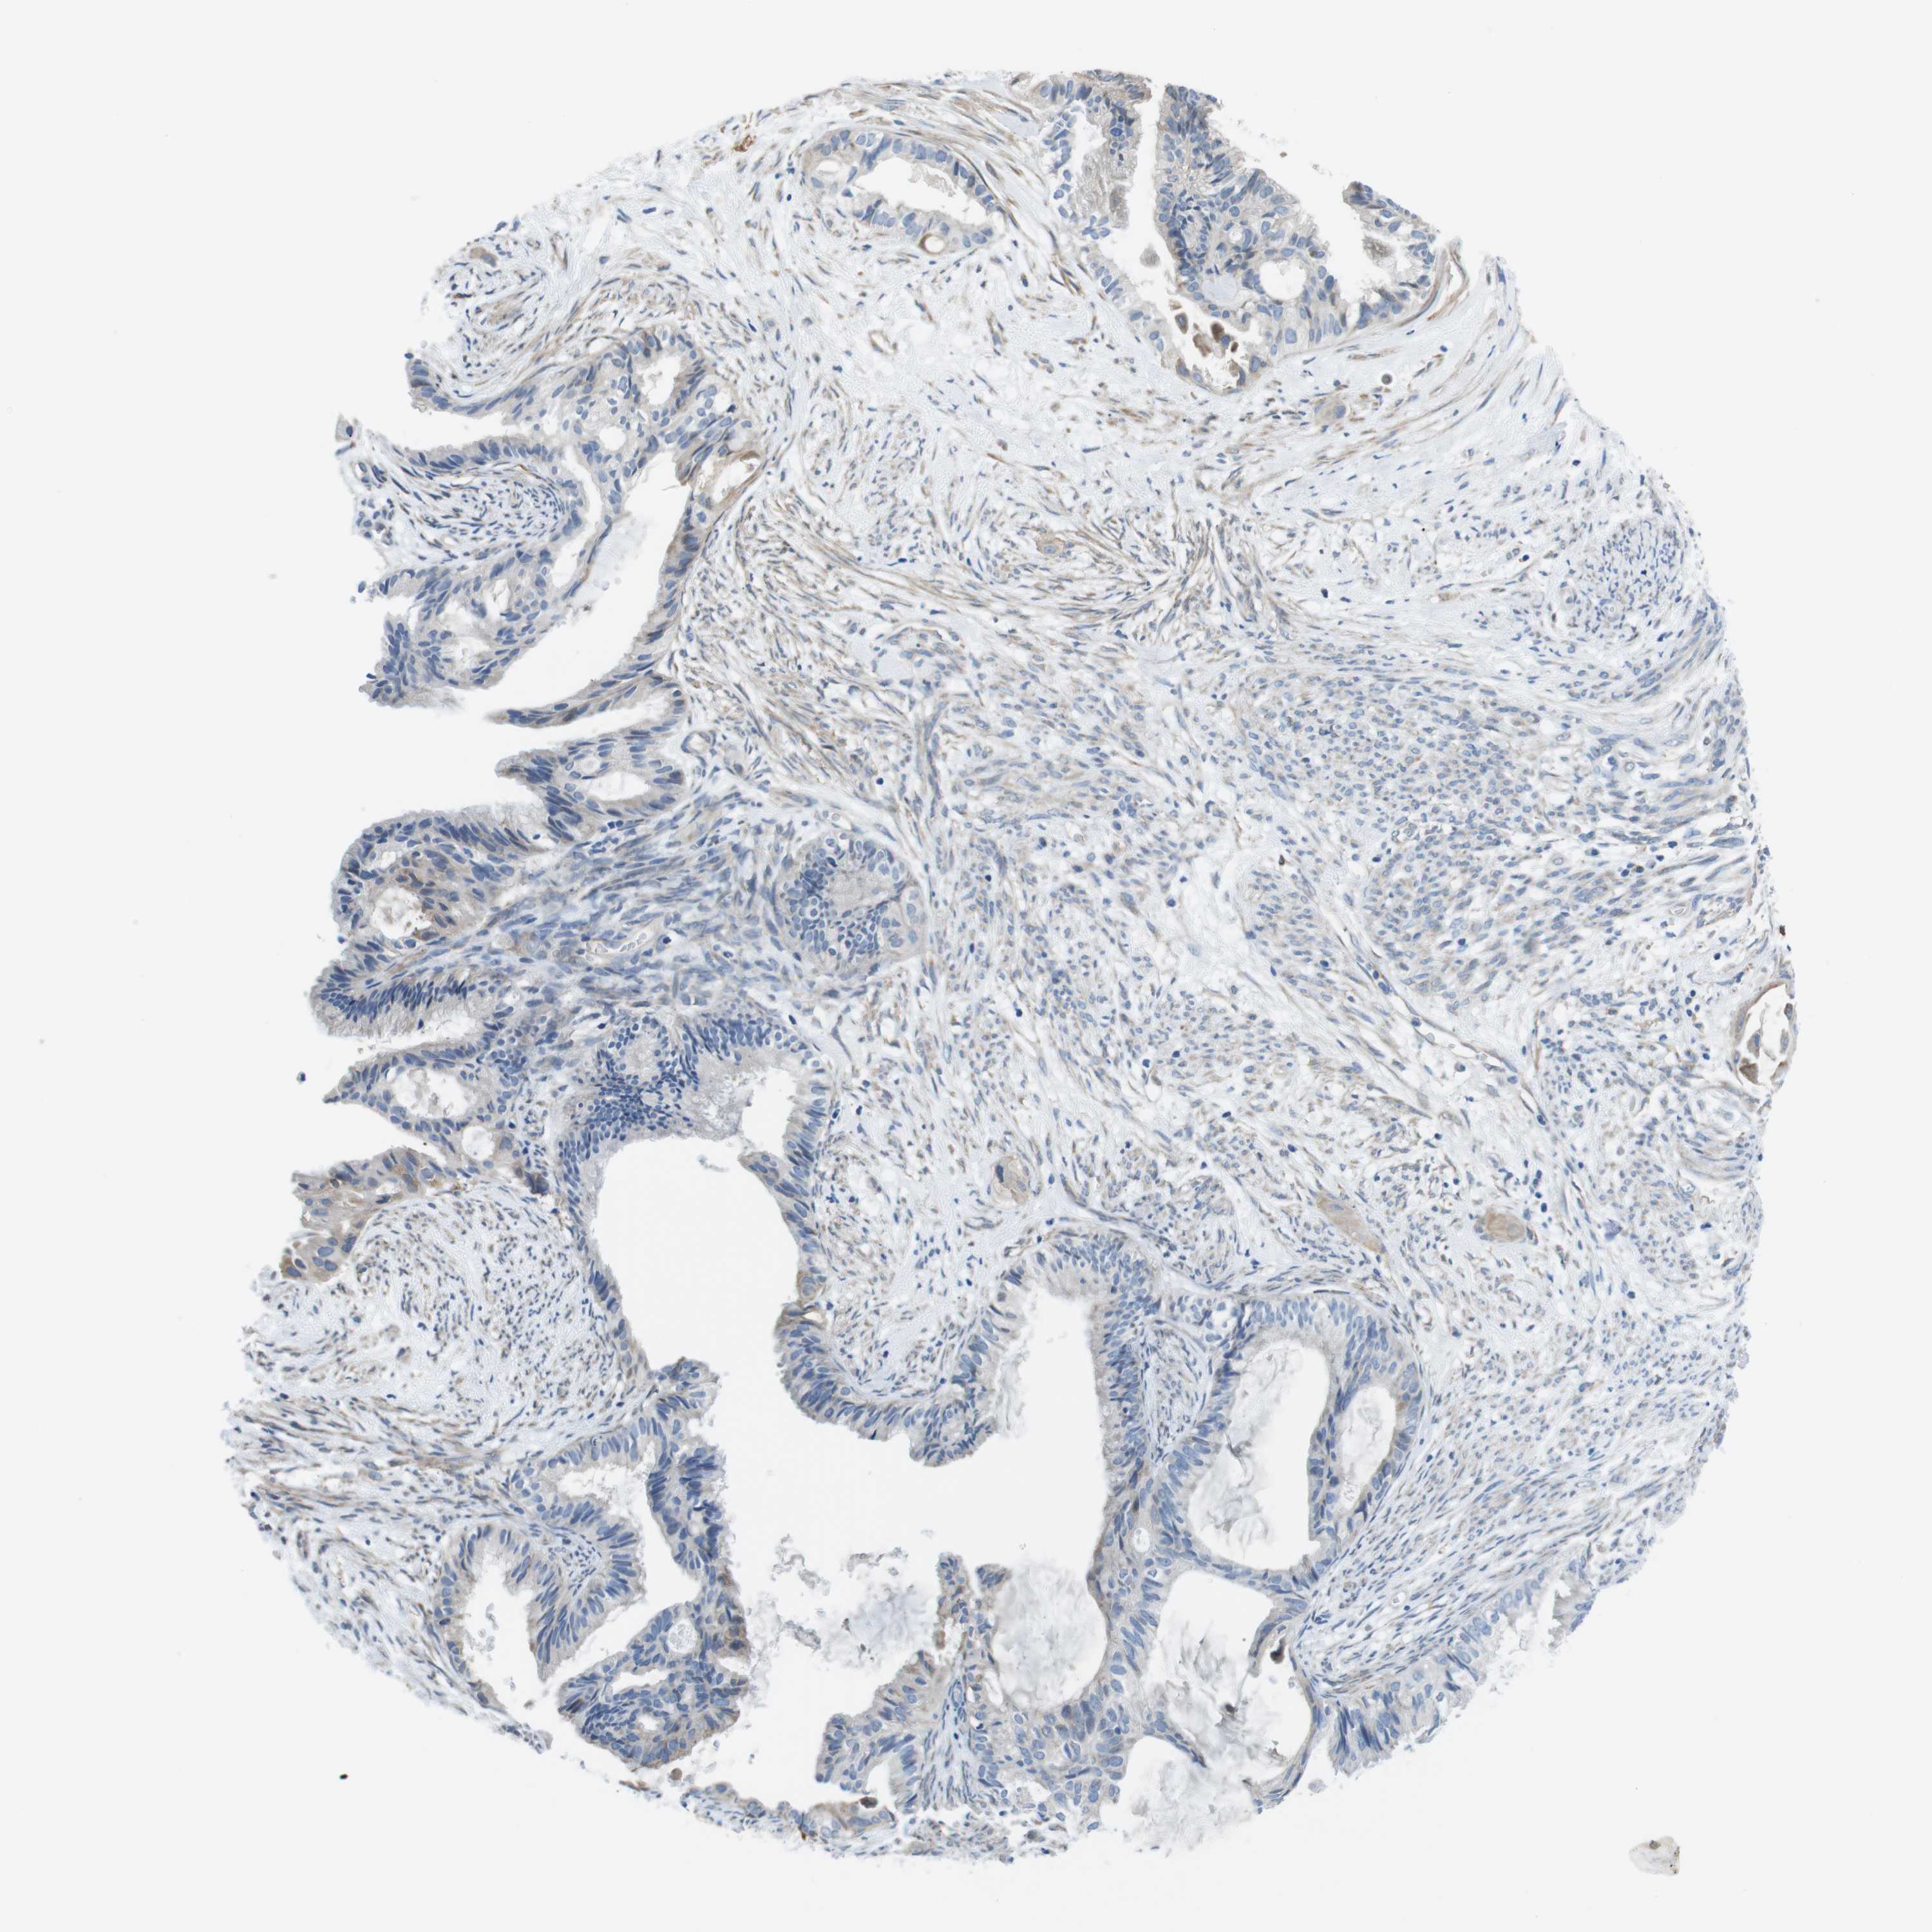

CERVICAL CANCER - Protein expressioni

A mouse-over function shows sample information and annotation data. Click on an image to view it in a full screen mode. Samples can be filtered based on level of antibody staining by selecting one or several of the following categories: high, medium, low and not detected. The assay and annotation is described here.

Note that samples used for immunohistochemistry by the Human Protein Atlas do not correspond to samples in the TCGA dataset.

Antibody stainingi

Antibody staining in the annotated cell types in the current human tissue is reported as not detected, low, medium, or high, based on conventional immunohistochemistry profiling in selected tissues. This score is based on the combination of the staining intensity and fraction of stained cells.

Each image is clickable and will lead to virtual microscopy that enables deeper exploration of all samples and also displays staining intensity scores, fraction scores and subcellular localization as well as patient and tissue information for each sample.

Antibody HPA014908

Staining

High

Medium

Low

Not detected

Intensity

Strong

Moderate

Weak

Negative

Quantity

>75%

75%-25%

<25%

None

Location

Nuclear

Cytoplasmic/membranous

Cytoplasmic/membranous,nuclear

Squamous cell carcinoma, NOS

Adenocarcinoma, NOS